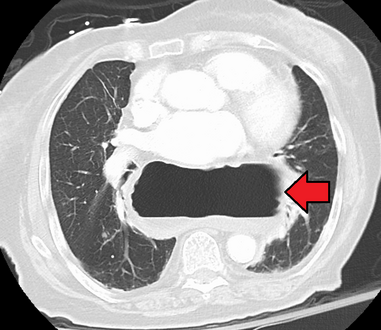

يتم تشخيص فتق الحجاب الحاجز عادةً من خلال سلسلة تصوير الجهاز الهضمي العلوي، التنظير الداخلي، قياس الضغط عالي الدقة، مراقبة درجة حموضة المريء، والتصوير المقطعي المحوسب. يسمح ابتلاع الباريوم كما في سلسلة تصوير الجهاز الهضمي العلوي لرؤية حجم المريء وموقعه وتضيقه. كما يمكنه تقييم حركات المريء. يمكن للتنظير الداخلي تحليل السطح الداخلي للمريء بحثاً عن التآكلات والقرح والأورام.

وفي الوقت نفسه، يمكن لقياس الضغط تحديد سلامة حركات المريء ووجود ارتخاء المريء. وتسمح اختبارات الأس الهيدروجيني بالتحليل الكمي لنوبات الارتجاع الحمضي. كما أن التصوير المقطعي المحوسب مفيد في تشخيص مضاعفات الفتق الحجابي مثل الالتواء المعدي، واسترواح الصفاق، واسترواح المنصف.[8]